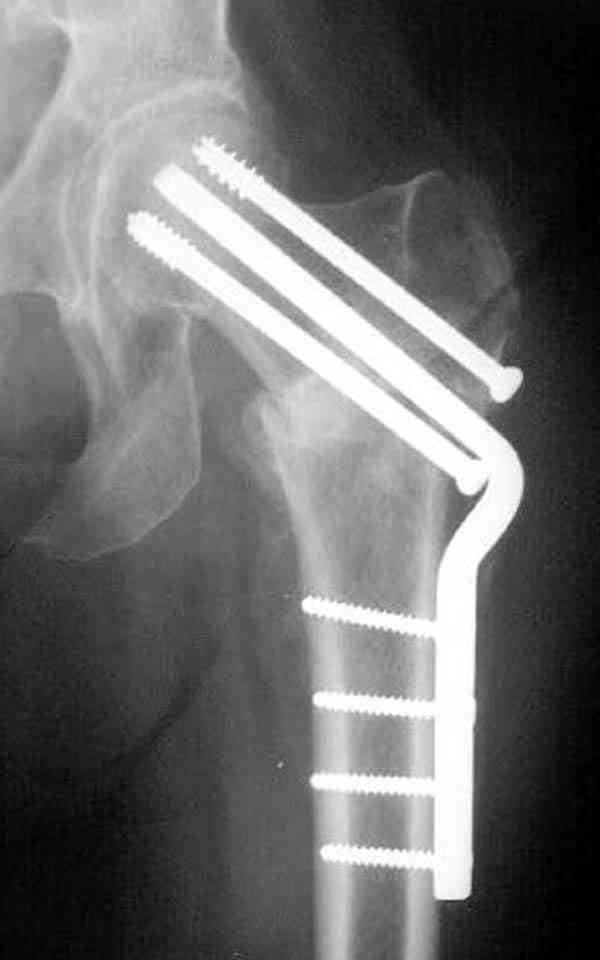

На Московской конференции в ноябре была продемонстрирована удивительная методика профилактического армирования шейки бедра у пациенток с остеопорозом и переломом контрлатеральной шейки в анамнезе.Странно, но дискуссии это сообщение не вызвало.Кто что думает об этом?

Спасибо, Антон. Я автор того сообщения по профилактическому армированию шейки бедренной кости, которое прозвучало на конференции, посвященной 50-летию создания АО. Мне тоже хотелось услышать вопросы по теме. Мы травматологи-ортопеды в первую очередь хирурги, а не терапевты. Почему в вопросе профилактики и лечения остеопороза мы ограничиваемся только консервативными методами лечения? Как можно практически научить больного не получать травмы, когда немало случаев возникновения переломов даже в постели. Первоначально идея армирования ШБК многих, при ком я озвучивал ее, шокировала, затем возникала дискуссия и большинство поддерживали эту идею. Мне бы очень хотелось развернуть дискуссию на странице этого сайта.

Кликните для загрузки файла P3230006.JPG

54KB (56062 bytes)

Спасибо за отклик.Хотелось бы для убедительности больше снимков, сделанных после падения, если это было, Ваших оперированных пациентов.Каюсь, но будучи в гриппозном состоянии, плохо прослушал детали Вашего доклада.Как ведут себя кость и фиксатор, если все же наступает перелом проксимального бедра, ведь перелом будет наверняка сложнее банального медиального.Я просил нашего гуру из США D.Kuldjanov прокомментировать тему,надеюсь он откликнется.В том углу зала, где я сидел,возник интерес к оценке Вашей работы экспертами страховых организаций.Ждем мнений.

Уважаемый Антон! У меня было всего три клинических наблюдения, снимки были продемонстрированы на московской конференции. Количества этих снимков хватило для подачи заявки, а затем и получения патента на изобретение. В свое время РОСПАТЕНТ потребовал подтверждения методики клиническими наблюдениями. У одной из больных действительно произошла повторная травма, и произошел подвертельный перелом на стороне армированной шейки бедренной кости (см. снимки). Это подтвердило основную идею изобретения - была сохранена и головка, и армированная шейка бедренной кости. Но тут не обошлось безпроблем. Анестезиологи отказались давать наркоз, а провести остеосинтез под м/а пластиной и винтом DHS не согласилась больная. Дальнейшее лечение скелетным вытяжением. На контр. Рентгенограмме через 2 месяца признаки формирования костной мозоли. Повторных обращений двух других пациентов не было. Для более детальных исследований и выводов необходимо значительно большее количество клинических наблюдений. Такие исследования могли быть проведены в условиях клиник медуниверситета. Напомню, я работаю в травмотделении провинциальной городской больницы. Насчет экспертов страховых компаний, так пусть они выскажут свое мнение. Армирование кости - это плановые операции по желанию больного, какие здесь могут быть противоречия? На армирование все больные, к моему удивлению, согласились довольно легко и сразу, поэтому остеосинтез и армирование были проведены в течение одной операции. С уважением А.М.

Кстати, очень сомнительна остеопорозность на правом оперированном бедре, отсутствует данные денситометрии с индексом остеопороза.

Коллега Челноков прав, здесь еще имеется риск перелома за счет ослабления латерального кортекса. Во время установки канюлированных шурупов за редким исключением спица вводится с одного раза, множественные попытки ослабляют латеральный кортекс, что станет источником перелома в этом месте.

В идеале для профилактики рефрактуры шурупы надо вводить не больше, чем под 130 градусным углом и не ниже уровня малого вертела.

Насчет биомеханических преимуществ одного шурупа тоже возникает вопрос. Если придерживаться канонов механики, для перелома шейки необходимо 3 паралельных шурупа, расположенных ближе к кортикальному слою шейки.

Здесь случай перелома из-за ослабления латерального кортекса через 3 недели после операции на шейке. Шурупы были установлены под большим углом, слабый латеральный кортекс не выдержал нагрузку.